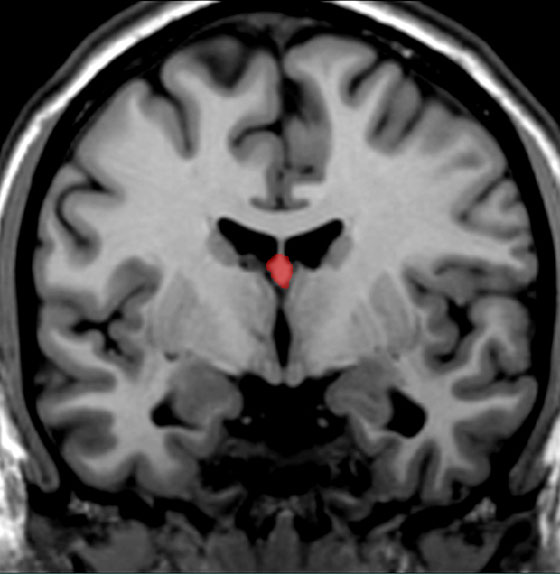

Incorrect! The correct answer is the fornix